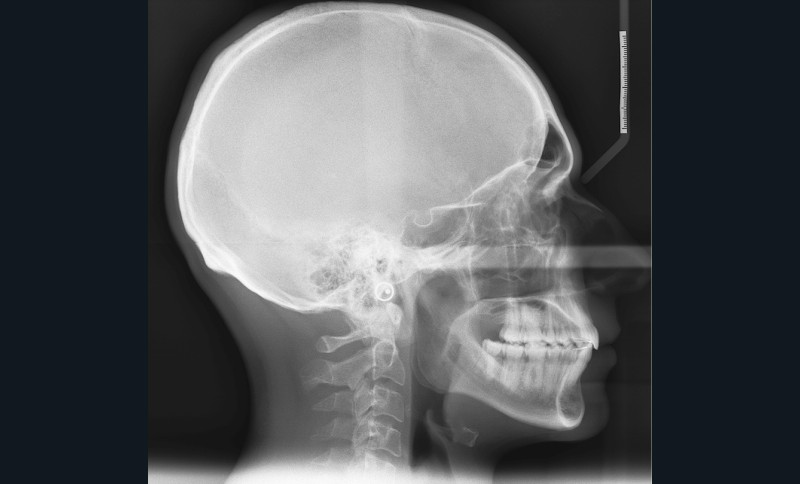

Diagnostic (fig. 1a-i)

Le patient consulte initialement pour des défauts d’alignement. L’examen clinique confirme l’existence d’un encombrement antérieur bimaxillaire, mais révèle aussi la présence d’une Classe II dentaire sévère, d’une exoclusion de la 27 et de troubles parodontaux (peu ou absence de papilles inter-dentaires). Sur le plan squelettique, le patient est relativement équilibré avec un profil harmonieux.